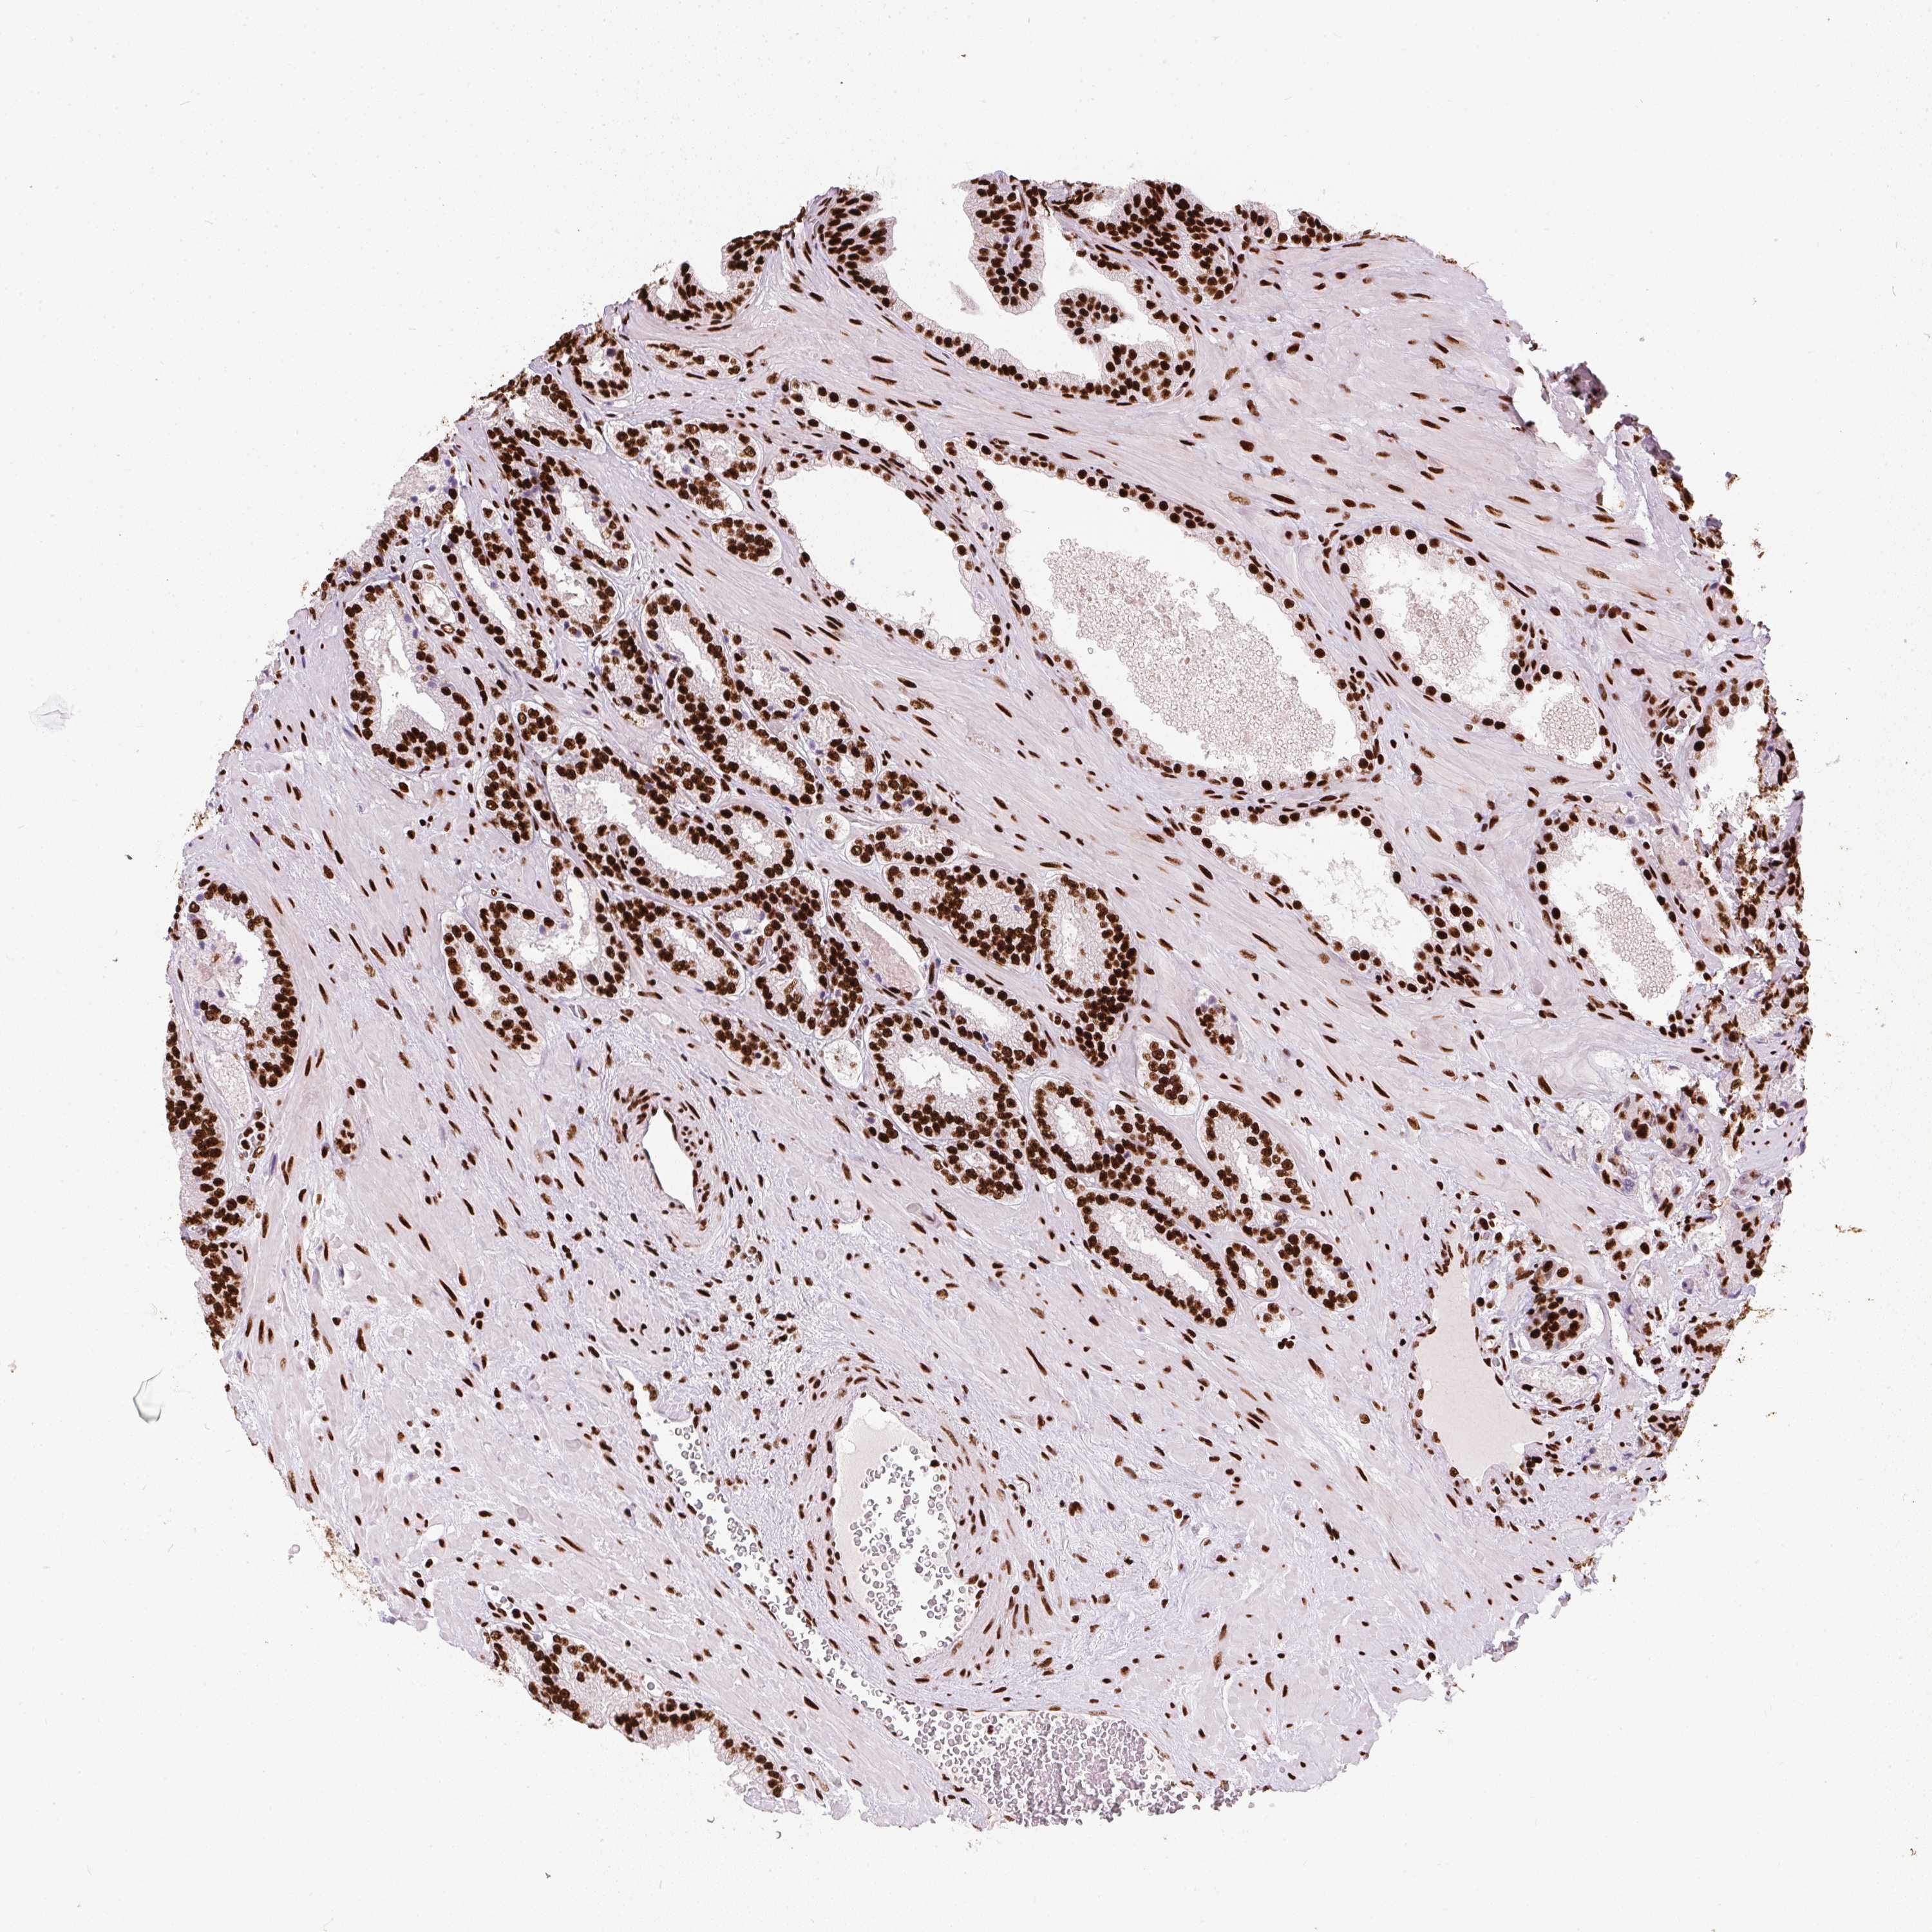

PROSTATE CANCER - Protein expressioni

A mouse-over function shows sample information and annotation data. Click on an image to view it in a full screen mode. Samples can be filtered based on level of antibody staining by selecting one or several of the following categories: high, medium, low and not detected. The assay and annotation is described here.

Note that samples used for immunohistochemistry by the Human Protein Atlas do not correspond to samples in the TCGA dataset.

Antibody stainingi

Antibody staining in the annotated cell types in the current human tissue is reported as not detected, low, medium, or high, based on conventional immunohistochemistry profiling in selected tissues. This score is based on the combination of the staining intensity and fraction of stained cells.

Each image is clickable and will lead to virtual microscopy that enables deeper exploration of all samples and also displays staining intensity scores, fraction scores and subcellular localization as well as patient and tissue information for each sample.

Antibody HPA062248

Staining

High

Medium

Low

Not detected

Intensity

Strong

Moderate

Weak

Negative

Quantity

>75%

75%-25%

<25%

None

Location

Nuclear

Cytoplasmic/membranous

Cytoplasmic/membranous,nuclear

Adenocarcinoma, High grade

Adenocarcinoma, NOS

Adenocarcinoma, Low grade